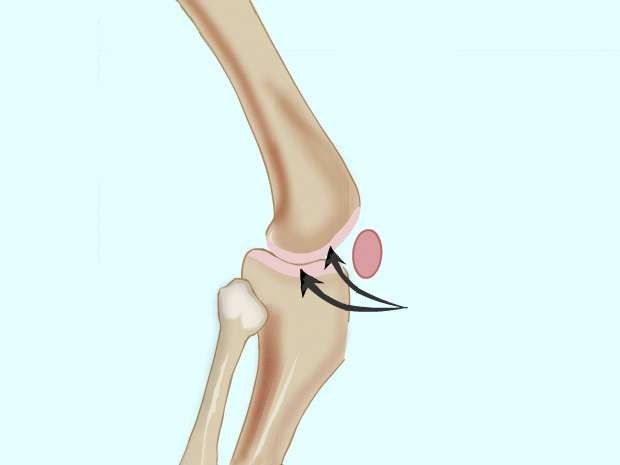

يعرّف البعض المفصل كنقطة اتصال عظامين. يشير آخرون إلى أنها نقطة حيث تتصل العظام لغرض تحريك أجزاء الجسم. السمسمويد عبارة عن عظام متضمنة في الأوتار، ولكنها غير متصلة بالعظام الأخرى. الرضفة (kneecap) هي أكبر السمسمويد. هذه العظام تختلف في العدد من شخص لآخر.

التوقف المشترك: المفصل المفصلي يشبه الباب، يفتح ويغلق في اتجاه واحد على طول طائرة واحدة. من الأمثلة على ذلك مفصل الكوع ومفصل الركبة.